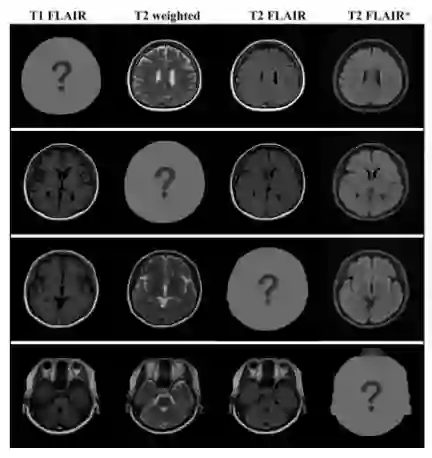

文章主要在三个数据集下进行实验测试,MR contrast synthesis 数据集是通过多动态多回波序列和来自 10 个受试者的附加 T2 FLAIR(流体衰减反转恢复)序列扫描总共 280 个轴脑图像。

在数据集中有四种类型的 MR 对比图像:T1-FLAIR (T1F),T2-weighted(T2w),T2-FLAIR (T2F) 和 T2-FLAIR (T2F)。前三个对比度是从磁共振图像编译(MAGiC,GE Healthcare)获得的,T2-FLAIR * 是通过第三对比度(T2F)的不同MR扫描参数的附加扫描获得的。MR contrast synthesis 数据集也是作者进行本次研究的目的性数据集。

文章还对不同域下的图像弥补缺失输入下进行了测试,得到的结果依旧是正向的: